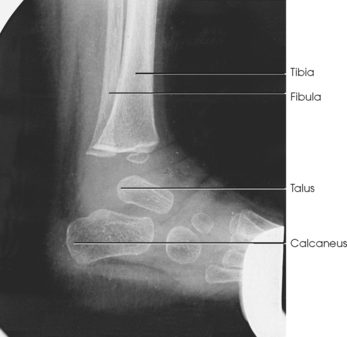

The talus, irregular in form and occupying the superiormost position of the foot, is the second largest tarsal bone (see Figs. 6-1 to 6-3). The talus articulates with four bones—tibia, fibula, calcaneus, and navicular bone. The superior surface, the trochlear surface, articulates with the tibia and connects the foot to the leg. The head of the talus is directed anteriorly and has articular surfaces that join the navicular bone and calcaneus. On the inferior surface is a groove, the sulcus tali, that forms the roof of the sinus tarsi. The inferior surface also contains three facets that align with the facets on the superior surface of the calcaneus.

The calcaneus is the largest and strongest tarsal bone (Fig. 6-3). Some texts refer to it as the os calcis. It projects posteriorly and medially at the distal part of the foot. The long axis of the calcaneus is directed inferiorly and forms an angle of approximately 30 degrees. The posterior and inferior portions of the calcaneus contain the posterior tuberosity for attachment of the Achilles tendon. Superiorly, three articular facets join with the talus. They are called the anterior, middle, and posterior facets. Between the middle and posterior talar articular facets is a groove, the calcaneal sulcus, which corresponds to a similar groove on the inferior surface of the talus. Collectively, these sulci constitute the sinus tarsi. The interosseous ligament passes through this sulcus. The medial aspect of the calcaneus extends outward as a shelflike overhang and is termed the sustentaculum tali. The lateral surface of the calcaneus contains the trochlea.

The calcaneus supports the talus and articulates with it by an irregularly shaped, three-faceted joint surface, forming the subtalar joint. This joint is classified as a synovial gliding joint. Anteriorly, the calcaneus articulates with the cuboid at the calcaneocuboid joint. This joint is a synovial gliding joint. The talus rests on top of the calcaneus (see Fig. 6-12). It articulates with the navicular bone anteriorly, supports the tibia above, and articulates with the malleoli of the tibia and fibula at its sides.

The ankle joint is commonly called the ankle mortise, or mortise joint. It is formed by the articulations between the lateral malleolus of the fibula and the inferior surface and medial malleolus of the tibia (Fig. 6-13, A). The mortise joint is often divided specifically into the talofibular and tibiofibular joints. These form a socket type of structure that articulates with the superior portion of the talus. The talus fits inside the mortise. The articulation is a synovial hinge type of joint. The primary action of the ankle joint is dorsiflexion (flexion) and plantar flexion (extension); however, in full plantar flexion, a small amount of rotation and abduction-adduction is permitted. The mortise joint also allows inversion and eversion of the foot. Other movements at the ankle largely depend on the gliding movements of the intertarsal joints, particularly the one between the talus and calcaneus.